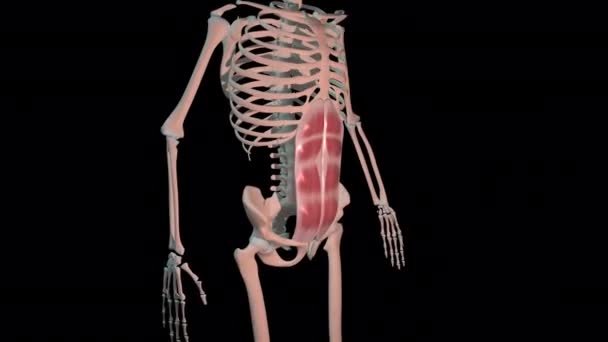

7-Piramidalis Kası

Piramidalis kası, mevcut olduğunda alt karın bölgesinde, rektus abdominis kası ve kas kılıfı arasında yer alan, eşleştirilmiş, üçgen şeklinde bir kas. Piramidalis kaslarının boyutu ve sayısı değişir; bazı kişilerde iki, bir veya hiç yok.

Araştırmacılar, nüfusunun yaklaşık %80’inde bir veya iki piramidalis kasının bulunduğunu tahmin etmekte.